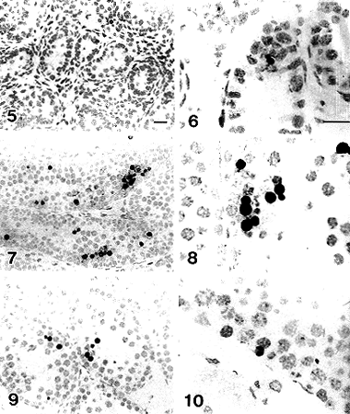

不加TdT或用TTP代替生物素染色的切片全无着色。由于显色液加用硫酸镍铵和氯化钴,反应有浅灰色的背底。考虑到正常细胞中有一定量的DNA末端存在,因而仅深黑色着染的胞核被定阳性。在分布上,TUNEL阳性细胞有从曲精小管腔面向基底面逐渐外移的趋势。生后0~1d,未见到阳性细胞(图5)。在生后4~7d,曲精小管上皮仅一层细胞,生殖细胞与支持细胞镶嵌存在,生殖细胞比例很低,TUNEL阳性细胞多为位于曲精小管腔面未与基膜接触的生殖细胞(图6);10~13d时,生殖细胞增殖活跃,曲精小管生精上皮变为3~5层,TUNEL阳性细胞最为多见,在各层中均有分布(图7,8);第18d时,TUNEL阳性细胞已经减少,虽在各层均可见到,但50%~60%位于第2层(图9);50d时,TUNEL阳性细胞进一步减少,70%以上位于基底层(图10)。TUNEL阳性细胞在各发育阶段的出现频率见图11。

图5 生后1d,TUNEL染色未见到阳性细胞 标尺示20μm

图6 生后7d,可见到较少量TUNEL阳性细胞,多位于曲细精管管腔面

图7 生后10d,见到较多的TUNEL阳性细胞,分布于生精上皮各层

图8 生后13d,也可见到较多的TUNEL阳性细胞,分布于生精上皮各层

图9 生后18d,TUNEL阳性细胞较10~13d时减少,多见于基底面第2层

图10 生后50d,TUNEL阳性细胞显著减少,多见于基底层。图5,7,9放大倍率相同;图6,8,10放大倍率相同;标尺示20μm

Fig.5 1 day after birth, no positive cells found with TUNEL staining.

Fig.6 7 day after birth, a few TUNEL-positive cells could be found to the lumen of the seminiferous tubules.

Fig.7 10 day after birth, a lot of TUNEL-positive cells could be found and distributed in the each layer of the germinal epithelium.

Fig.8 13 day after birth, many TUNEL-positive cells could also be found in the layers of the germinal epithelium.

Fig.9 18 day after birth, TUNEL-positive cells were fewer than that in the day of 10-13, and were mainly found in the second basal layer of the epithelium.

Fig.10 50 day after birth, TUNEL-positive cells were significantly reduced and mainly found in the basal layer of the germinal epithelium.

Fig. 5,7,9 are in the same amplification; Fig.6,8,10 are in the same amplification. Bar=20μm

统计结果显示,前、后各相邻年龄组间凋亡细胞的出现频率有显著性差异。